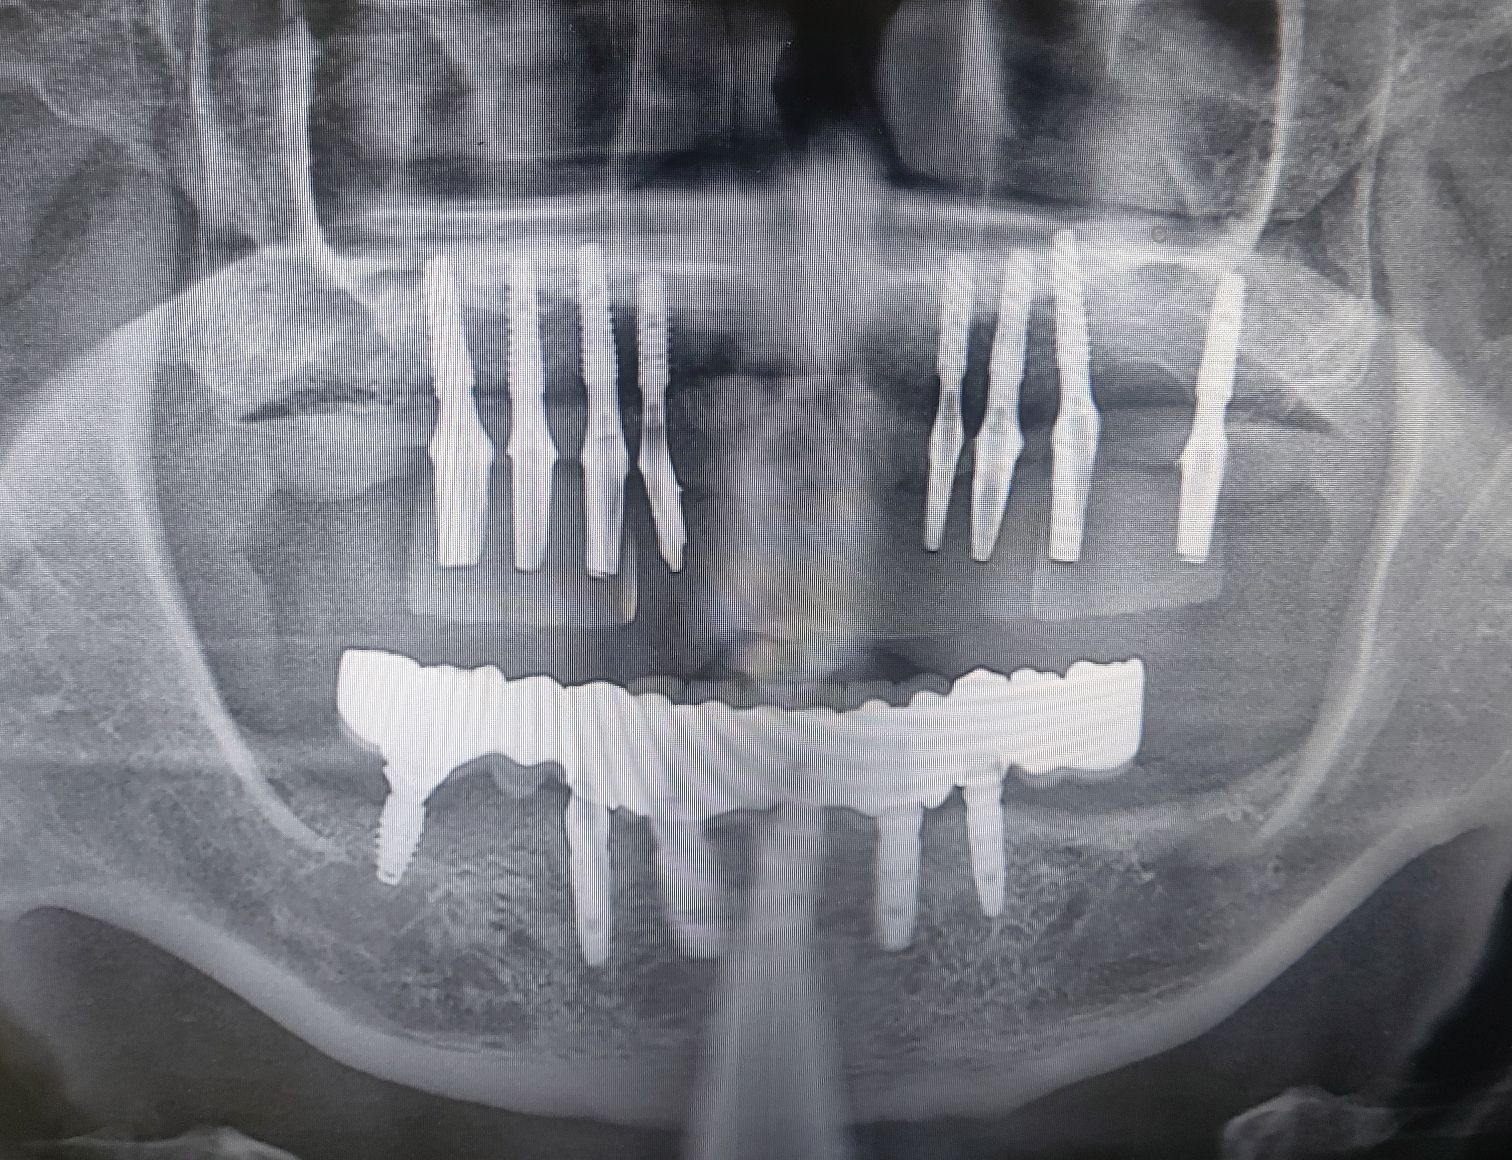

제가 초진부터 금일 완성까지 약 13개월 정도가 소요되었습니다.

상악 2차 수술시 잘 유착된 임플란트를 보며 좋은결과를 예상했고 좋은 결과로 마무리 지었습니다.

일년이란 긴 시간동안 참 고생많으셨습니다.